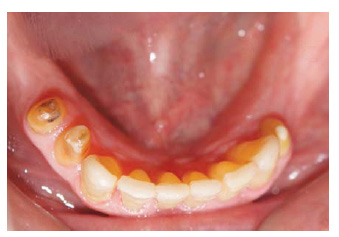

Se realizarón los exámenes clínicos, radiográficos y tomográficos necesarios llegando a los siguientes diagnósticos: Periodontitis crónica localizada moderada en las piezas 12,22,35 y severa en la pieza 15, deformidades y condiciones mucogingivales en rebordes edéntulos: Seibert III: Sextante IV y VI. Lesiones cariosas en piezas: 13,22,24,25, pérdida de sustancia dental causada por: Piezas talladas sin provisionales en piezas 34,35,44,15,12,21,22,24,25. Destrucción coronaria pieza 13, Diagnóstico pulpar: tratamiento de conductos previo piezas 15, 13, 12, 22, 24, Movilidad dental grado 3 en la pieza 15. Asimismo presentó un Desorden Funcional Oclusal teniendo como características: Edéntulo parcial: superior e inferior, Alteración de la guía anterior y disminución de dimensión vertical. (Figura 1 a y b).

Figura 1 a: Aspecto clínico del maxilar superior.

Figura 1 b: Aspecto clínico del maxilar inferior.